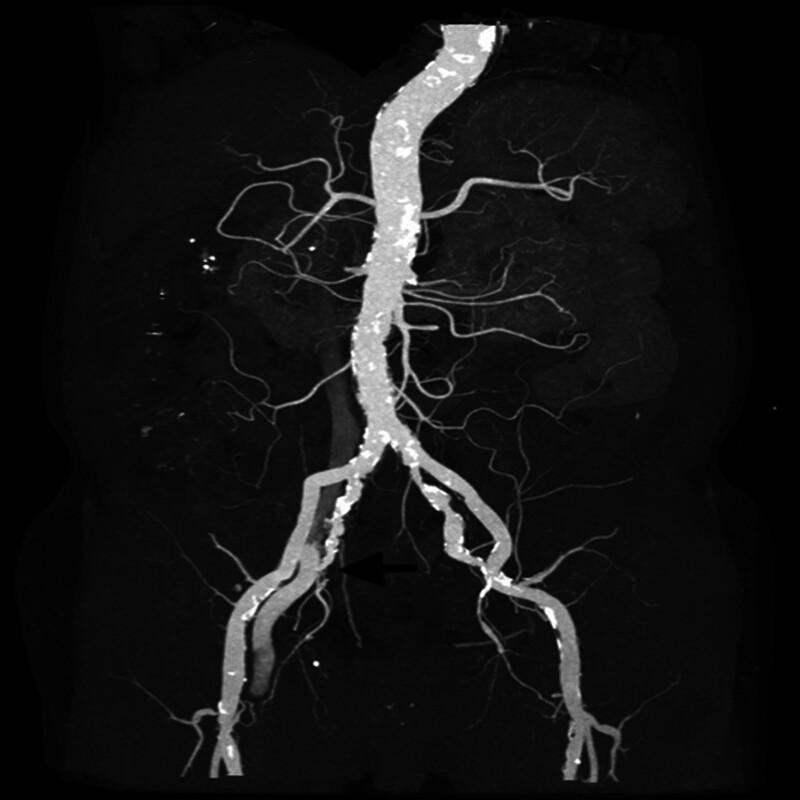

Herein, we report the case of a patient with diabetes and end-stage kidney disease (ESKD) who presented with an iliac arteriovenous fistula as a complication of hemodialysis catheter insertion into the right femoral vein. Two years after hemodialysis catheter removal, the patient was admitted to our institution with swelling of the right lower limb and calf pain.

The patient was subsequently diagnosed with an iliac arteriovenous fistula by computed tomography angiography and angiography.

随后通过计算机断层血管造影和血管造影,该患者被诊断为髂动静脉瘘。